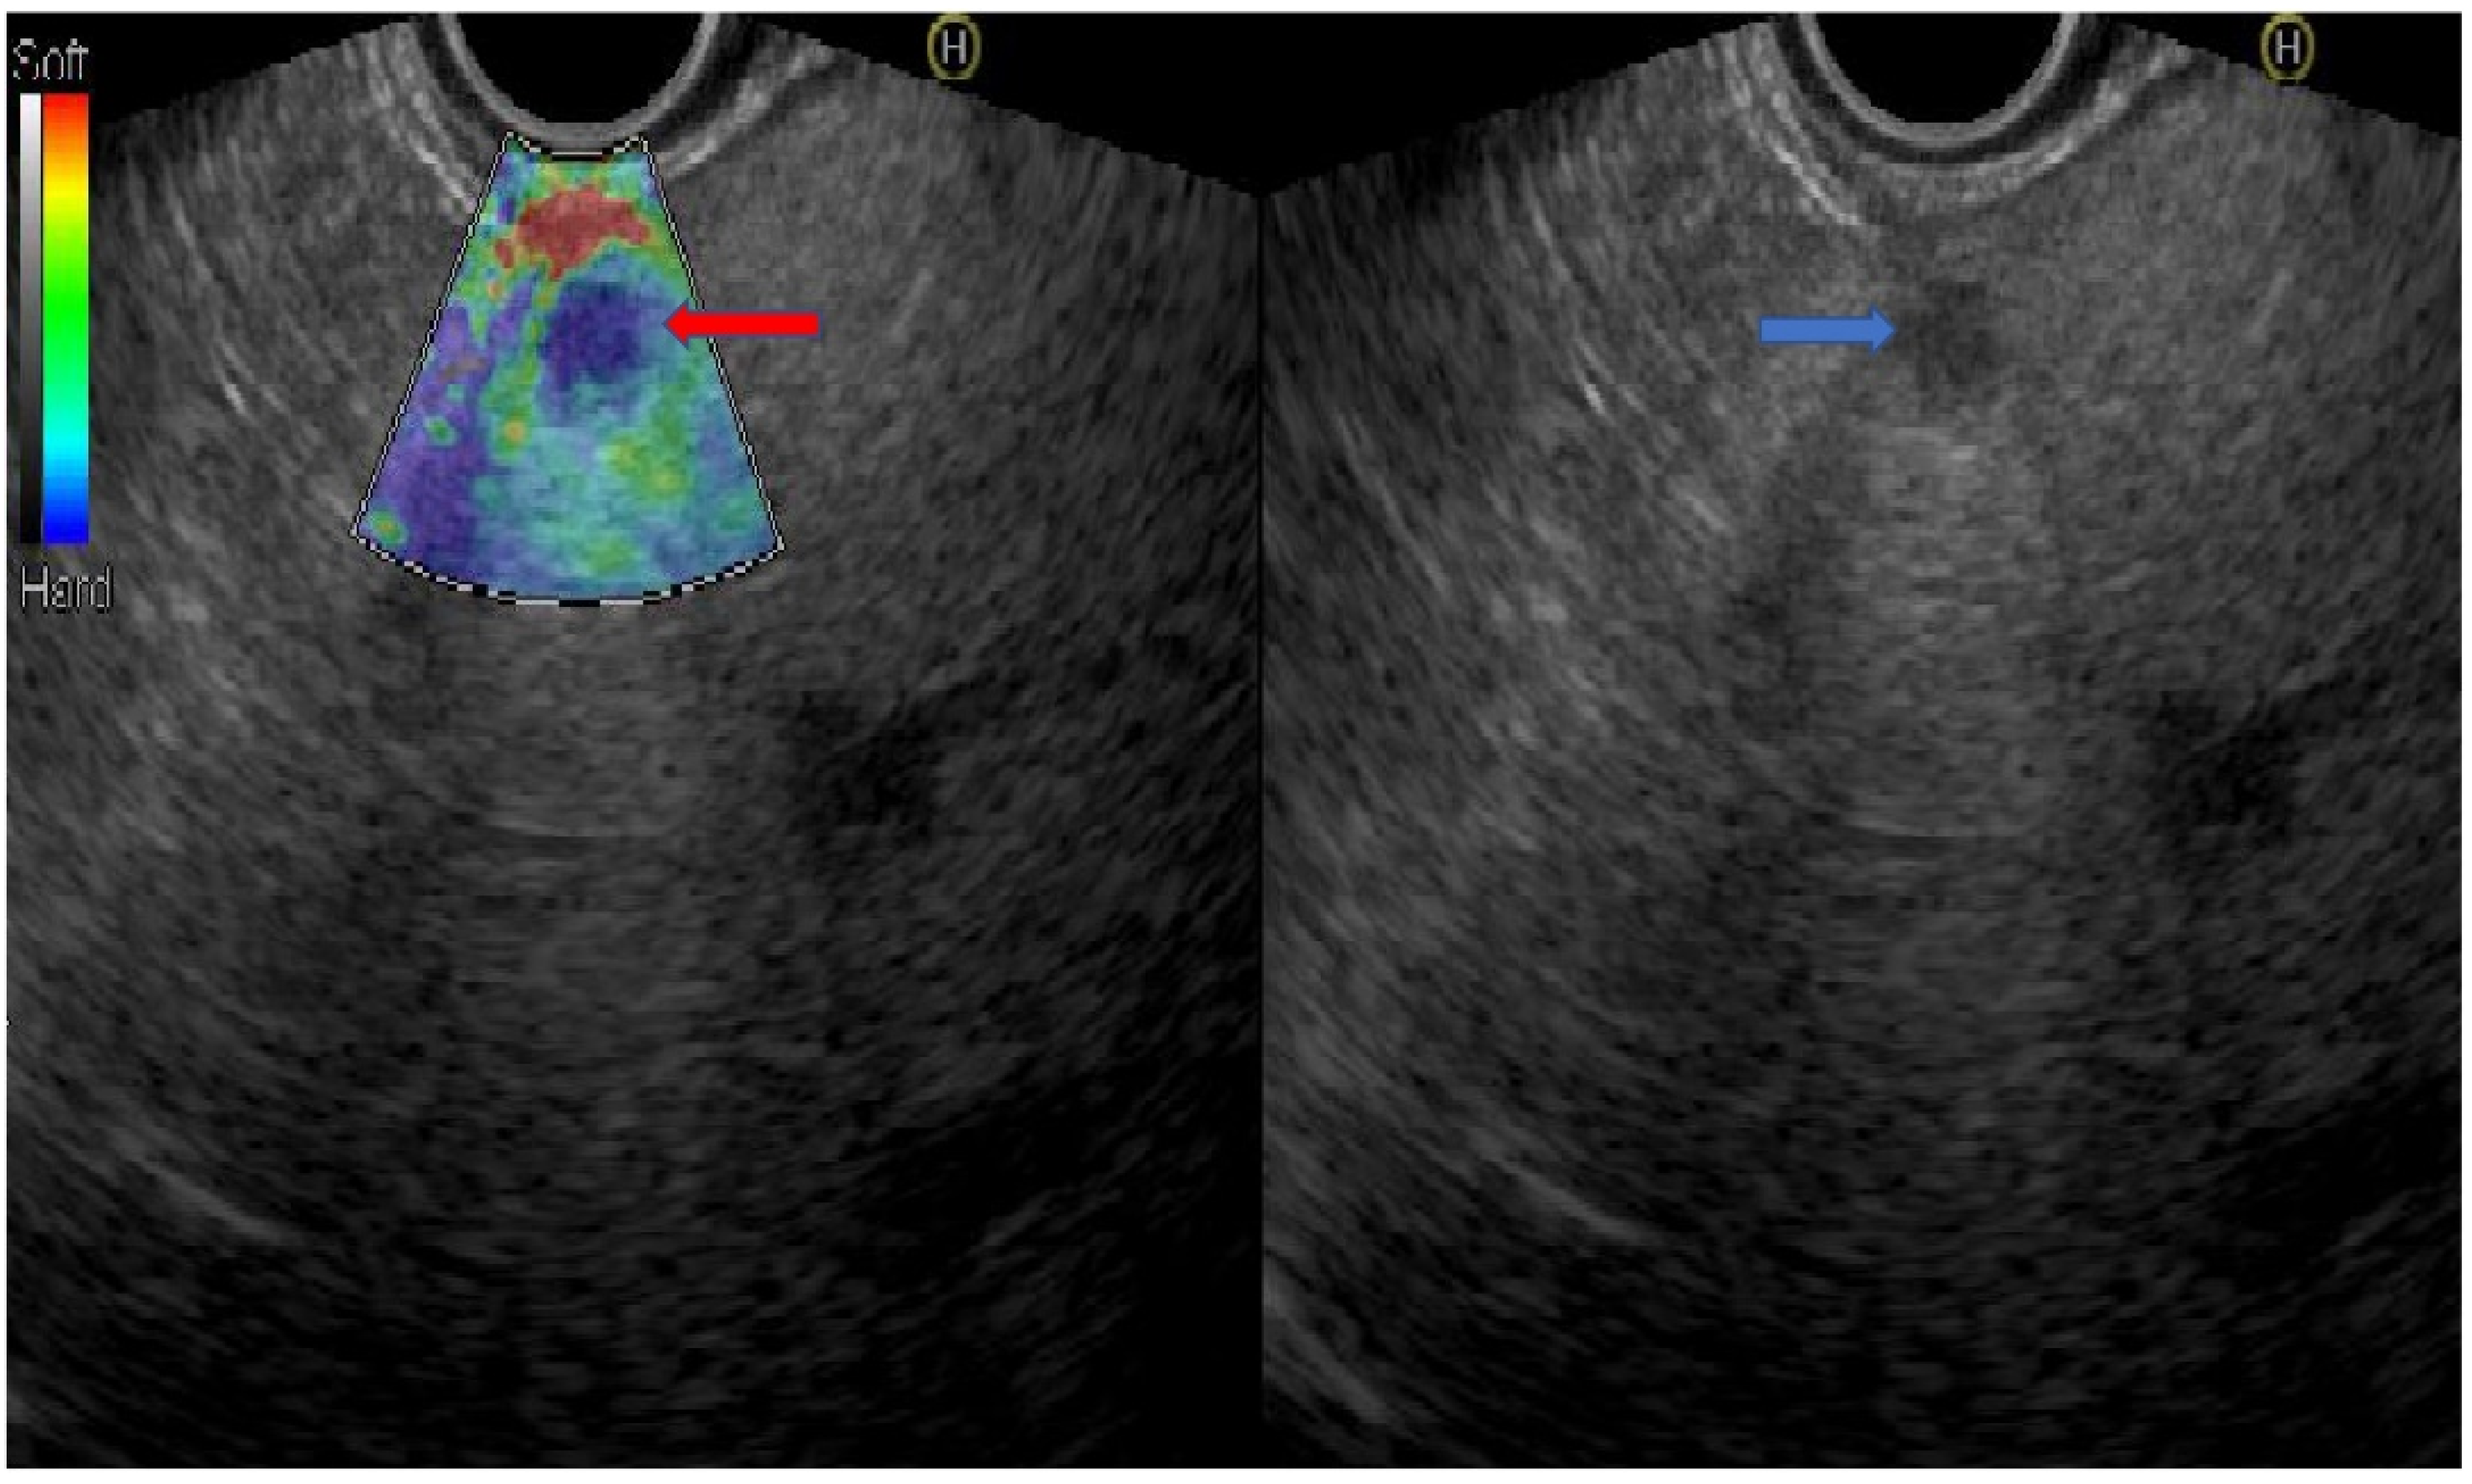

Figure 1.

A patient with metastatic pancreatic adenocarcinoma to the liver. The blue arrow shows the liver metastasis by linear echoendoscope. The red arrow shows the lesion by real-time EUS-elastography in a blue color reflecting the hardness and stiffness of the lesion (the picture was supplied from the gastroenterology department at Galilee Medical Center).